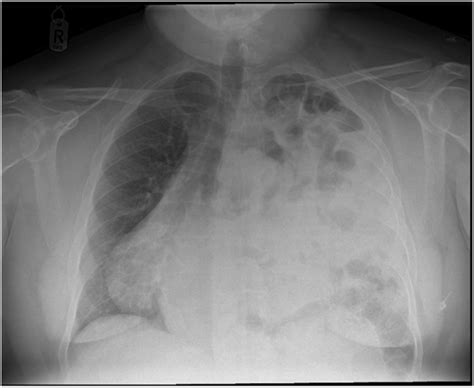

Chest X-ray: Provides a basic view of the chest and can show the presence of a hernia.

• Respiratory Distress: The hernia can compress the lungs, making it difficult to breathe.